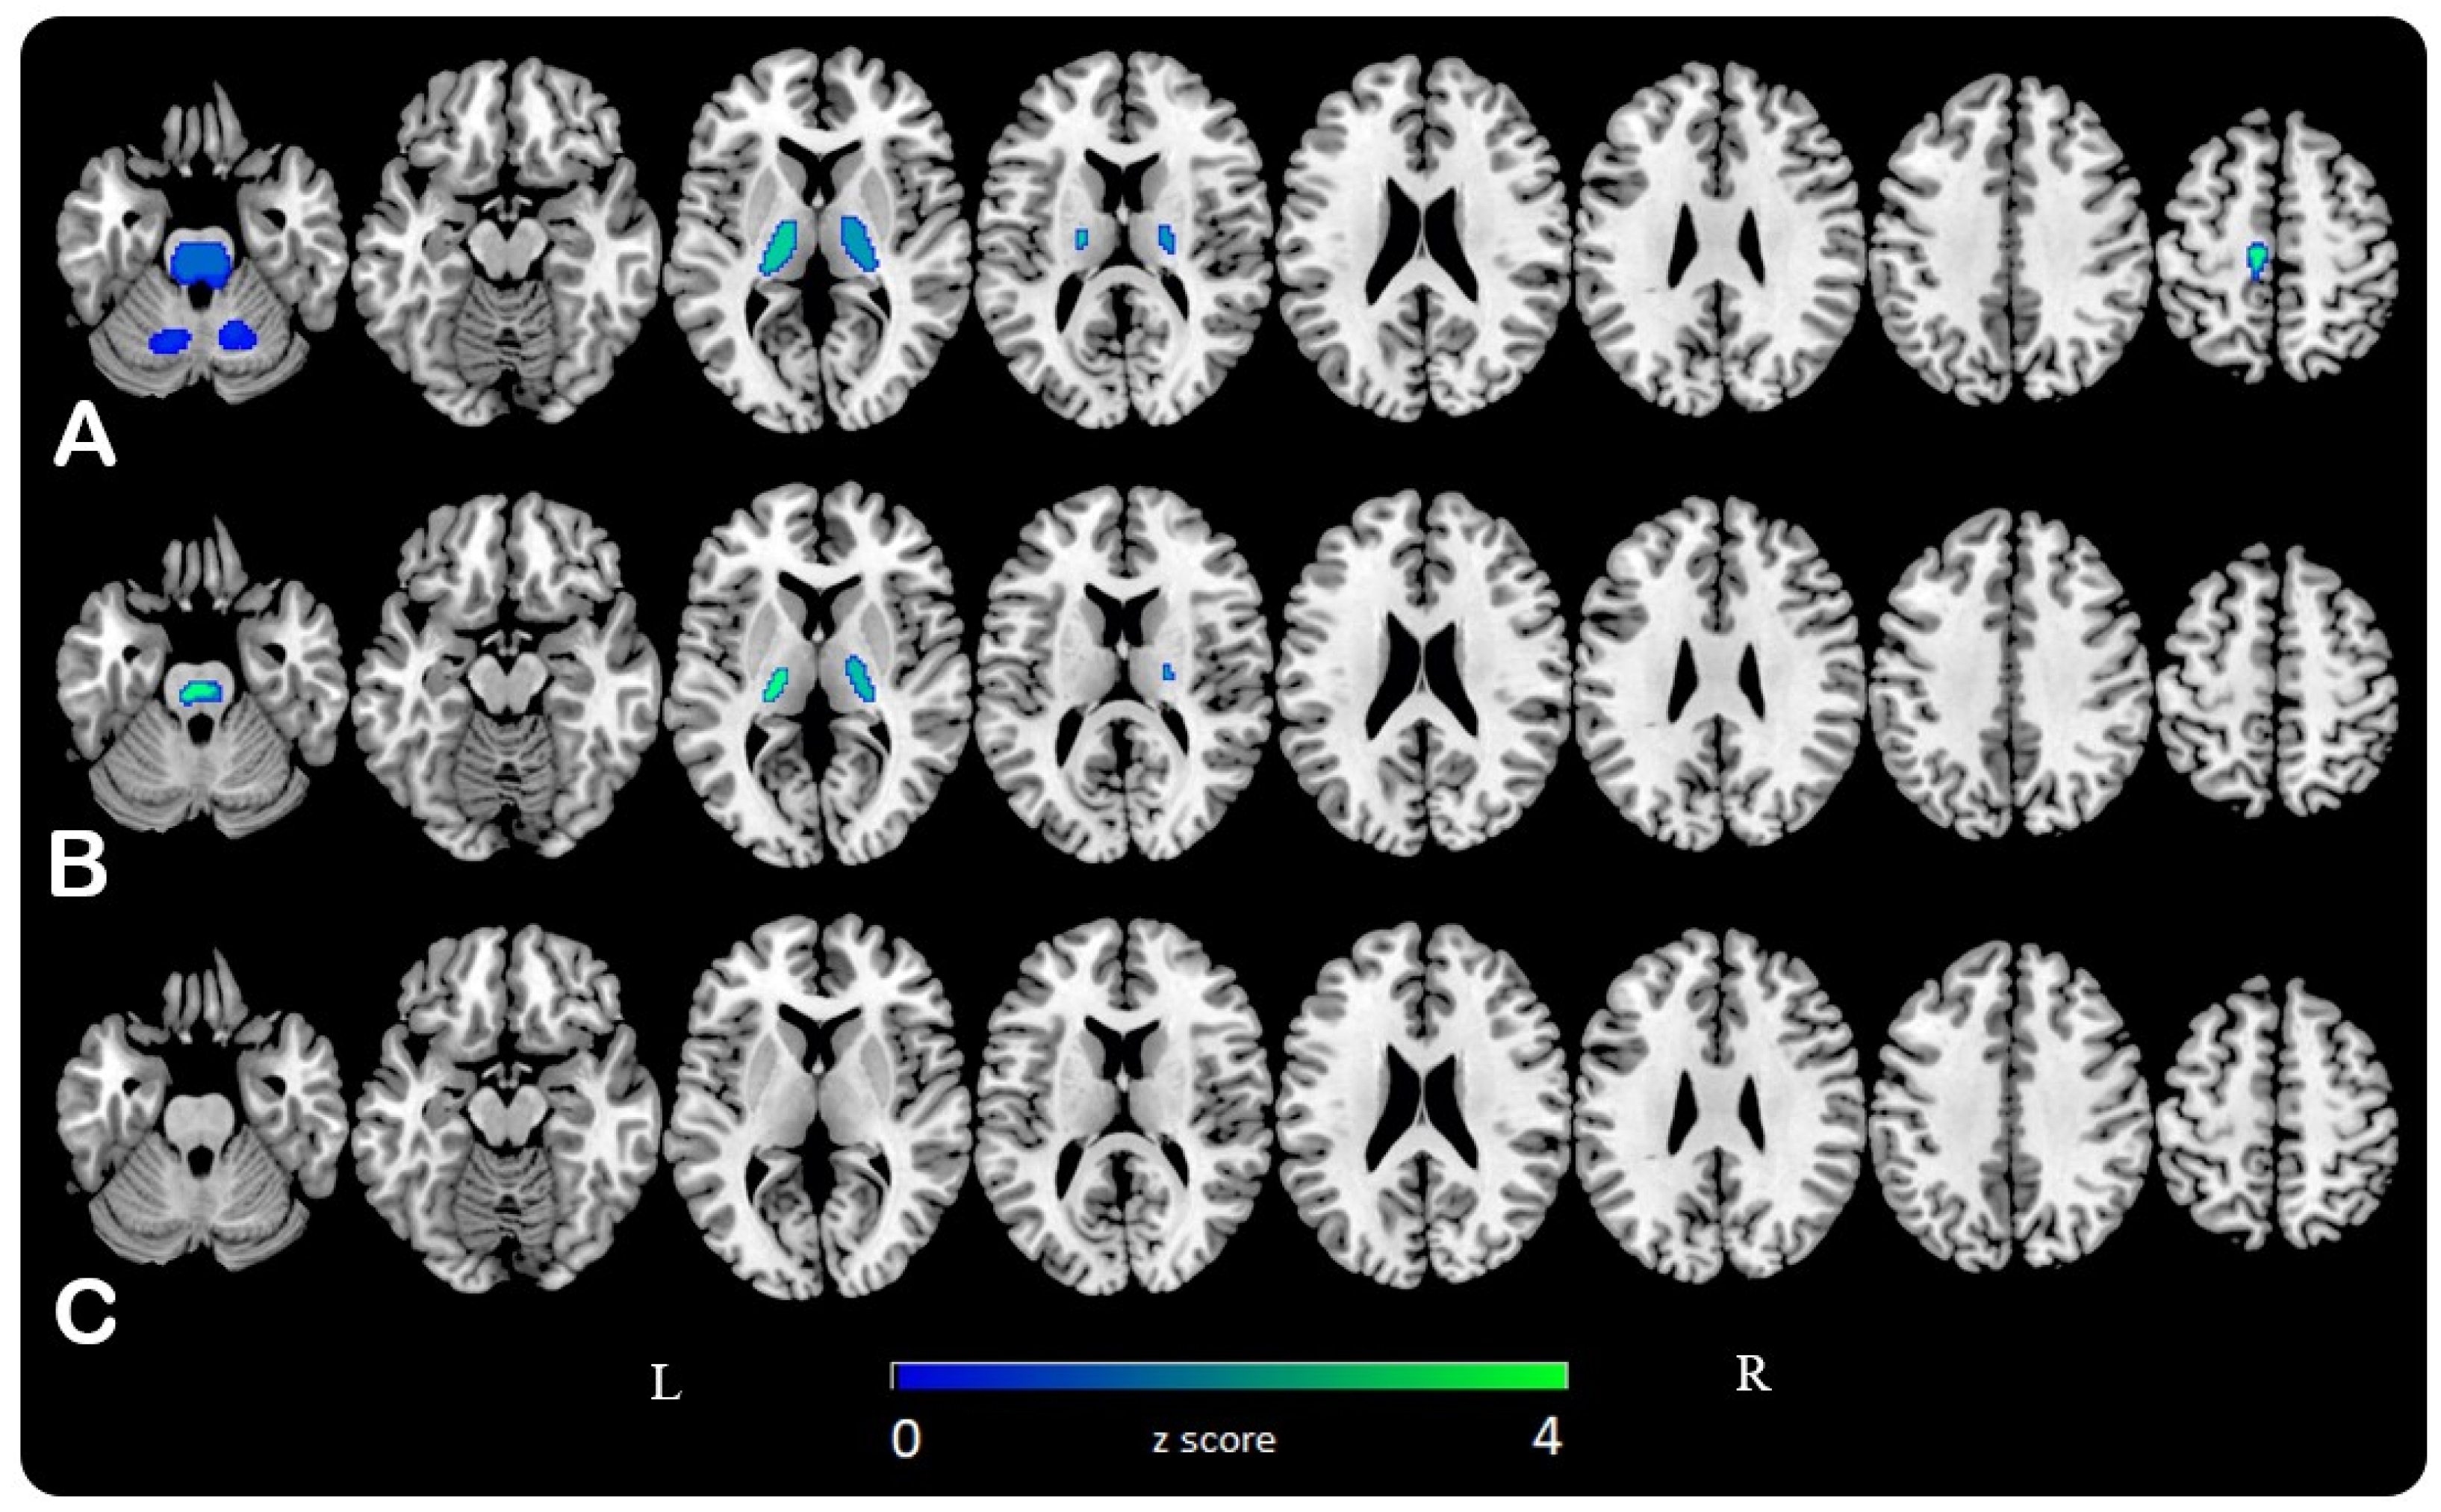

3.1. SPM Analysis